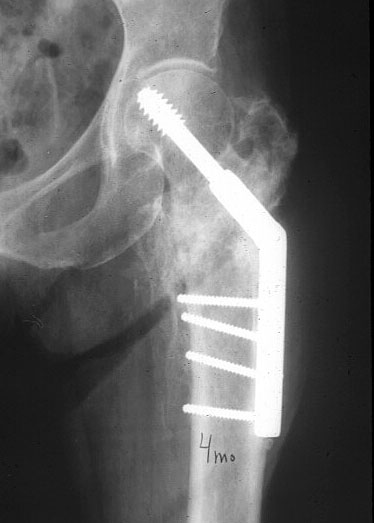

Вот пример наших американских коллег про DHS. Видно, как стелескопировались отломки, хотя поначалу был оставлен диастаз.

Фиксатор или DHS 130 градусов или PFN с короткой ножкой. Если DHS, то шуруп должен находиться в центре шейки и дополнительно еще простой длинный шуруп против ротации в проксимальной части шейки над шурупом DHS. Полную нагрузку на ногу начать через 6 недель.

Классический Intertrochanteric fracture - самое простое - это Dinamic Hip Screw and Plate - после этого через днь-два начинаем ходьбу с полной нагрузкой и укрепление мышц-и в течение месяца бабушка вернется к своему огороду :)